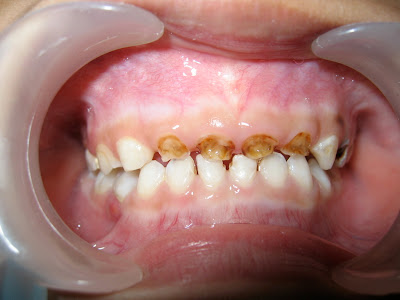

hallo bloggers… anda terganggu dengan gigi si kecil yang hitam-hitam seperti ini?

pertama-tama jaringan karies yang kehitam-hitaman

akan dibersihkan dahulu…